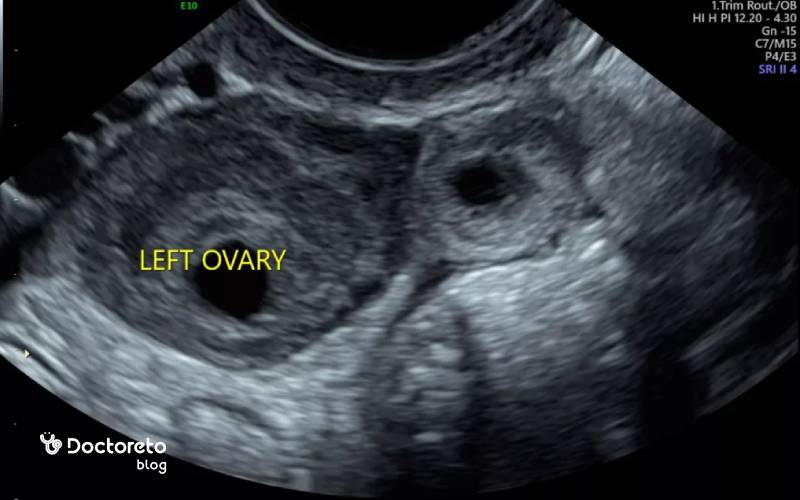

سونوگرافی بارداری خارج از رحم

سونوگرافی واژینال یکی از دقیقترین روشها برای تشخیص بارداری خارج از رحم است. در سونوگرافی حاملگی خارج از رحم، پزشک میتواند بررسی کند که آیا کیسه بارداری یا ساک حاملگی در داخل رحم قرار دارد یا خیر. اگر کیسه بارداری در رحم دیده نشود، یا در جایی غیر از رحم (مثلاً در لوله فالوپ) مشاهده شود، احتمال بارداری خارج از رحم وجود دارد. این روش بهخصوص در کنار آزمایش خون میتواند به تشخیص سریع و دقیق کمک کند و از بروز عوارض جدی جلوگیری نماید.